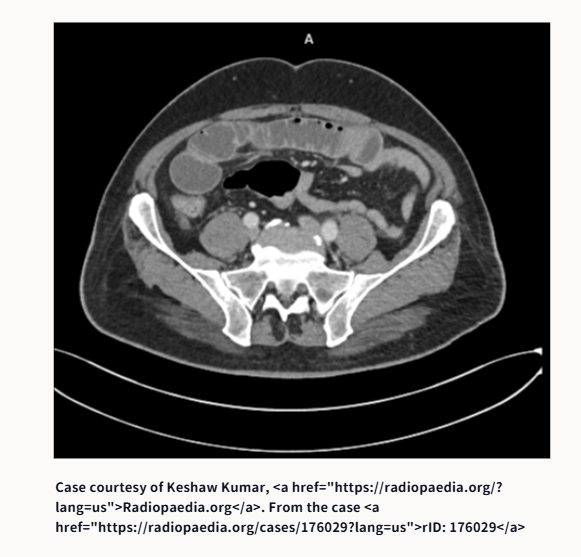

①腸閉塞です。原因は何でしょうか?

①腸閉塞の原因は、鼠径ヘルニア嵌頓でした